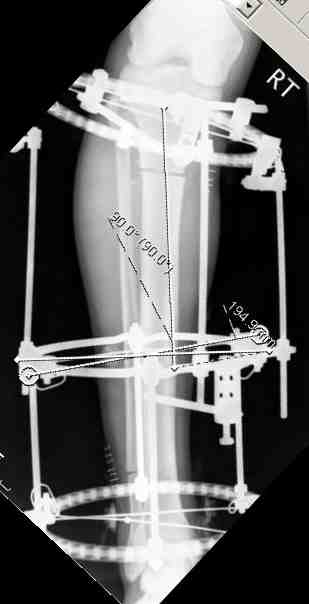

Выше представлены рентгенограммы открытого оскольчатого перелома нижней трети голени

X-rays of Compound Comminuted # Distal/3 Lt Tibia

Операционные снимки перед и после наложения аппарата Илизарова

In operation room before and after Ilizarov apparatus has been applied

Послеоперационные рентгенограммы

Postoperative X-rays

В нижнем ряду представлены рентгенограммы после окончательной репозиции.

And final reduction after Hexapod program has been finished